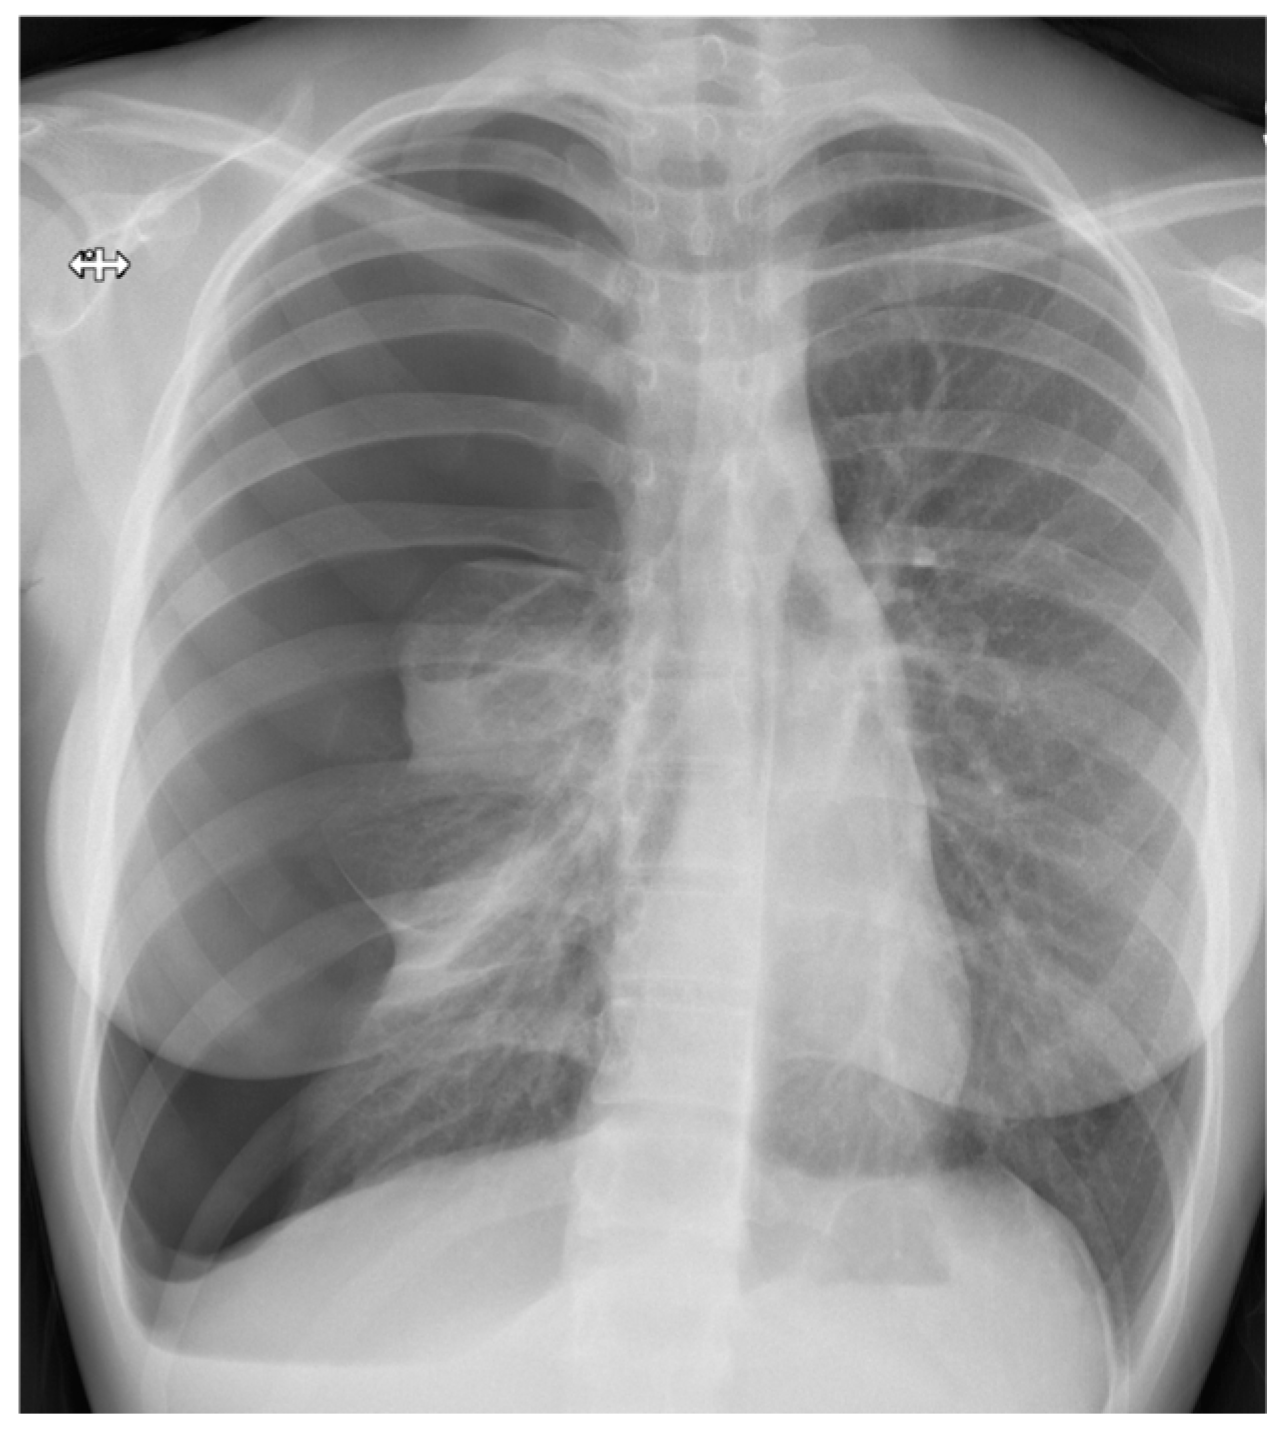

3.3. Chest Radiography

3.5. Size of Pneumothorax